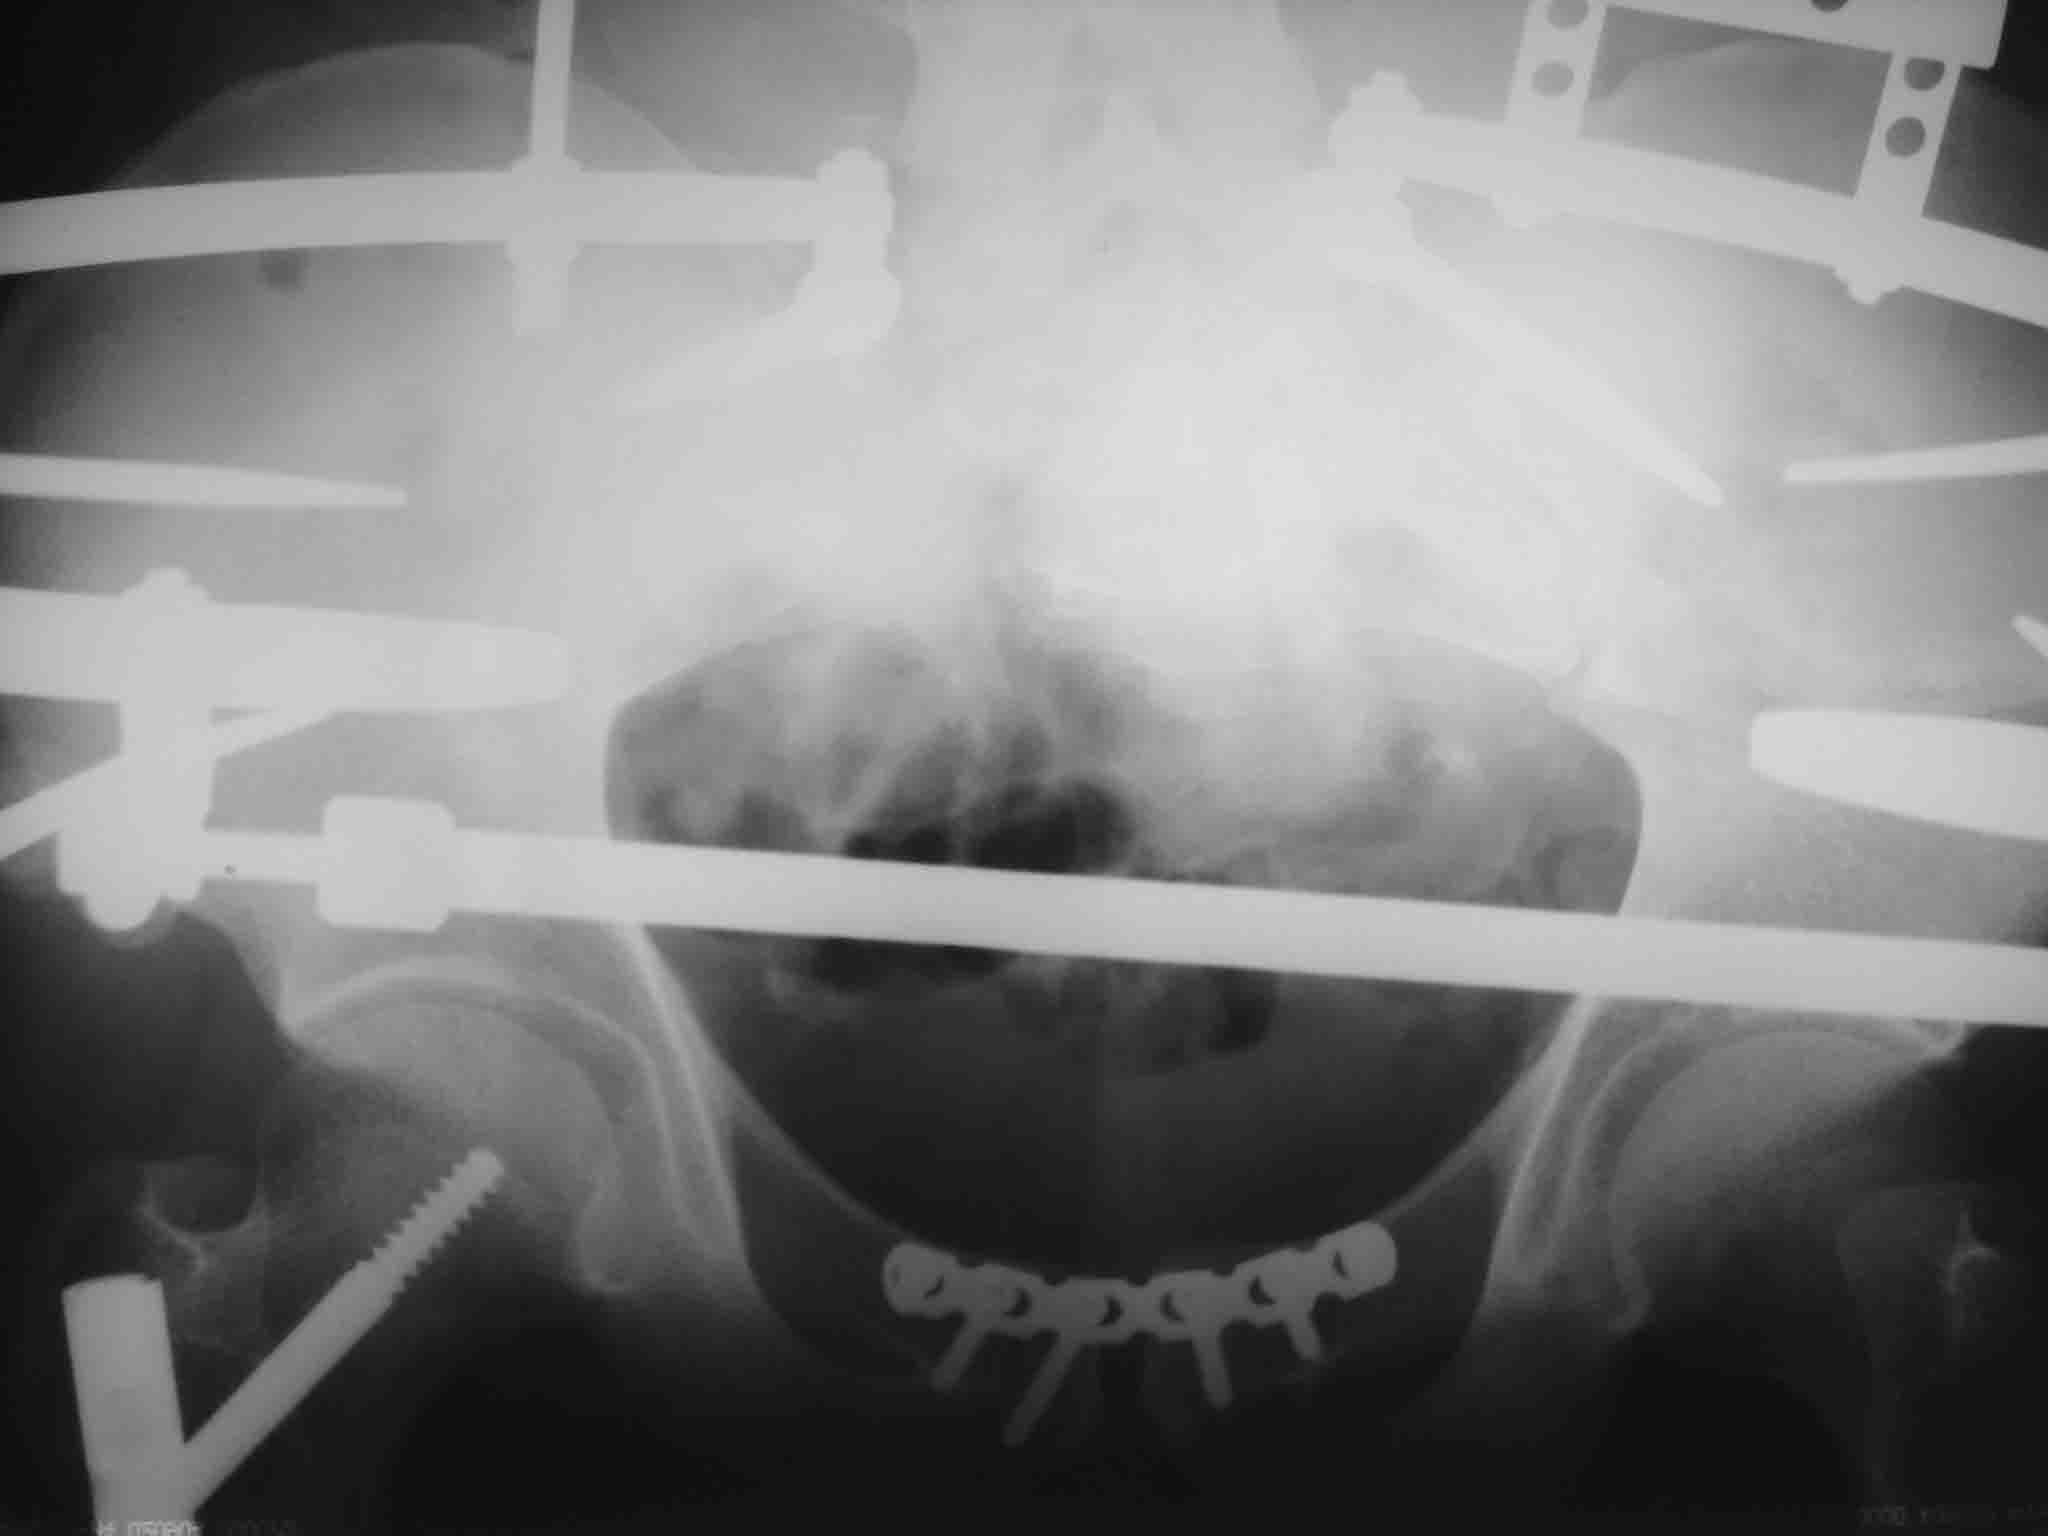

[Ortho] разрыв лонного сочленения